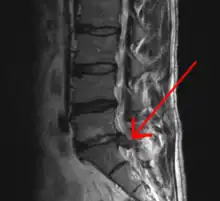

An intervertebral disc has a gelatinous core surrounded by a fibrous ring.[36] When in its normal, uninjured state, most of the disc is not served by either the circulatory or nervous systems – blood and nerves only run to the outside of the disc.[36] Specialized cells that can survive without direct blood supply are in the inside of the disc.[36] Over time, the discs lose flexibility and the ability to absorb physical forces.[27] This decreased ability to handle physical forces increases stresses on other parts of the spine, causing the ligaments of the spine to thicken and bony growths to develop on the vertebrae.[27] As a result, there is less space through which the spinal cord and nerve roots may pass.[27] When a disc degenerates as a result of injury or disease, the makeup of a disc changes: blood vessels and nerves may grow into its interior and/or herniated disc material can push directly on a nerve root.[36] Any of these changes may result in back pain.[36]